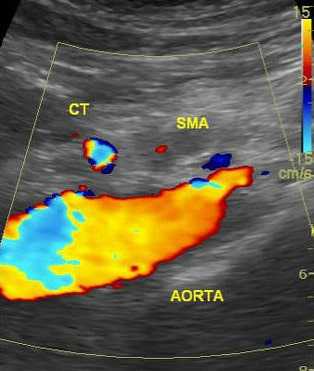

6. УЗДГ (чувствительность 80%). Метод особенно эффективен при подозрении на стеноз нескольких сосудов.

УЗДГ не рекомендуется проводить при острой ишемии, ожирении, кишечной непроходимости, когда нарушение кровотока можно выявить только в проксимальных отделах.

Высокую прогностическую ценность имеют отклонения от нормы пиковой систолической скорости кровотока (S), которая ориентировочно составляет более 275 см/с для ВБА или 200 см/с для НБА (по некоторым данным > 300 см/с).

Нормальная скорость после приема пищи должна увеличиться примерно на 20% и более.

Ненормальный постпрандиальный ответ интерпретируется как увеличение пиковой систолической скорости менее чем на 20%.

Тяжелым считает стеноз артерий, составляющий более чем 60-70%, который выявляется при триплексном сканировании. При этом на допплерограмме ниже места поражения ламинарный поток исчезает и появляется турбулентный поток.

УЗИ брюшной аорты позволяет выявить тромбоз брыжеечной артерии или чревного ствола. Преимуществом метода является его быстрая доступность и отсутствие осложнений. Брюшная аорта осматривается в продольном и в поперечном срезе в режиме цветового картирования. Определяется скорость кровотока по аорте и ее ветвям. Метод обладает достаточно высокой чувствительностью, но его результаты зависят от опыта врача, проводящего исследование и правильной интерпретации полученных данных.